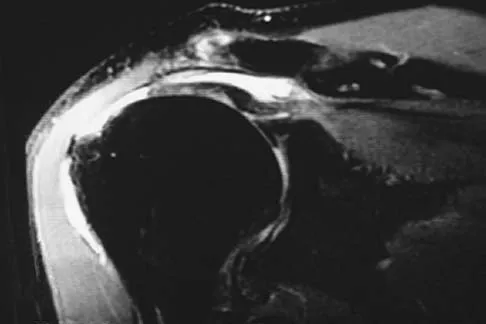

Question 28:

Figure 14 shows an intra-articular gadolinium-enhanced MRI scan of a 52-year-old woman who has stopped playing tennis because of pain in her left shoulder while serving. What is the most likely diagnosis?

Options:

- Superior labral detachment

- Os acromiale

- Partial-thickness rotator cuff tear on the articular side

- Medial subluxation of the long head of the biceps

- Moderate arthrosis of the glenohumeral joint

Correct Answer: Partial-thickness rotator cuff tear on the articular side

Explanation:

The MRI scan shows increased signal intensity along the deep fibers of the supraspinatus near its insertion. This is typical of tendinosis and a probable partial-thickness rotator cuff tear. Herzog RJ: Magnetic resonance imaging of the shoulder. Instr Course Lect 1998;47:3-20.